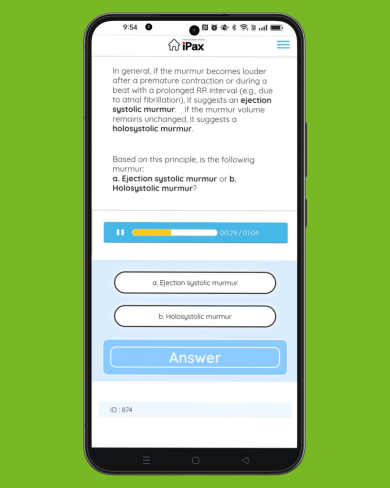

Daily quiz

2025/06/17

On June 17, a question was presented regarding heart murmurs following premature contractions. Ejection murmurs become louder after a premature beat, whereas holosystolic murmurs show no change in volume. Which type of murmur was presented in the quiz? (June 17, 2025)

この記事を読む